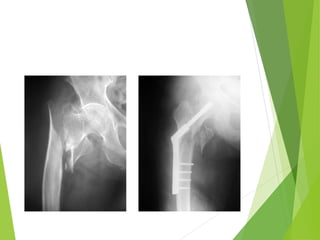

Fractura subcapital

Jóvenes

 “ salvemos la epifisis

femoral ”

 Osteosíntesis con

tornillos canulados

7.0

 Descarga 3 – 6 meses

 Controles estrictos

 Siempre posibilidad

complicaciones: - NA